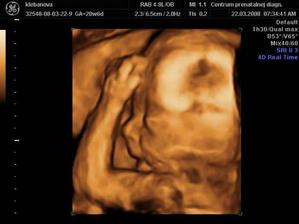

a vonavy kvietocek - anjelicek, mala princeznicka Kristianka Sarah a treti kvietocek je uz v brusku